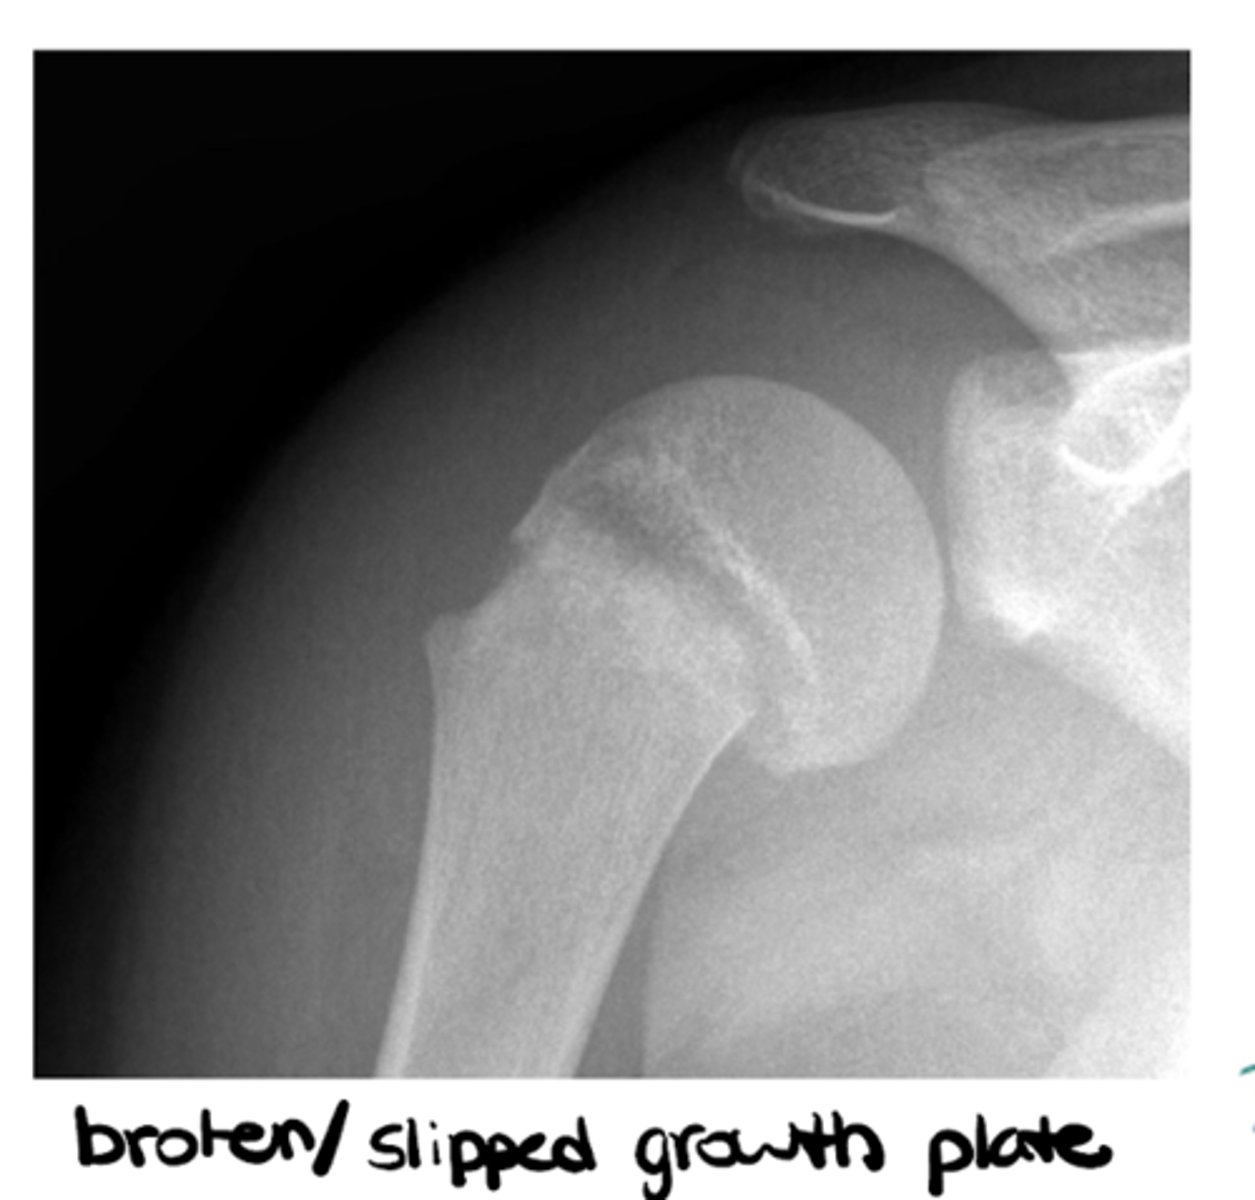

What are epiphyseal plates? What do they indicate?

Cartilage in the middle of bone that gives the bone room to grow and solidifies over time -- think pediatric patients

3. Epiphyseal plates